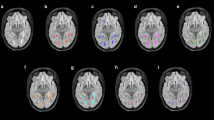

Lesion-level analysis

The two expert readers labelled 164 CE lesions in total (GT labeling). When compared to the GT labeling on a lesion-level, the AI system detected 73 lesions correctly (TP), 91 lesions were missed (FN), and 22 lesions were misclassified as CE lesions (FP). Table 3 shows the results of the manual lesion-level analysis for TP and FN. FN lesions were predominantly located in the infratentorial location (p = 0.020). Relatively more TP lesions showed a ring enhancement, while FN lesions predominately showed punctual enhancement (p = 0.093). Mean aCNR was significantly lower in FN cases compared to TP cases (p = 0.001). Mean maximum diameter of FN lesions was significantly smaller compared to TP cases (p = 0.001). In Fig. 2, two representative TP lesion segmentations are shown. The 3D CNN correctly labeled the subcortical, ring enhancing lesion in the right occipital lobe (Fig. 2a) and the juxtacortical, punctual enhancing lesion in the left frontal lobe (Fig. 2b). Whereas in Fig. 3, typical FN lesions, that are relatively small, at low contrast, and often in the infratentorial location, are provided. Common alternative diagnoses for FP lesions were pulsation artifacts in the temporal lobe (n = 3), cerebral vessels (n = 2), meningioma (n = 2), and hyperintensities in a tumor resection cavity (n = 2) (Fig. 4).

Two representative true positive lesions. The 3D CNN correctly labeled the subcortical, ring enhancing lesion in the right occipital lobe (a) and the juxtacortical, punctual enhancing lesion in the left frontal lobe (b). FLAIR and T1C as well as zoomed views of the CE lesions without and with segmentation masks are shown. CNN, convolutional neural network; T1C, T1-weighted post-contrast; CE, contrast-enhancing

Two representative false negative lesions. Relatively small, low-contrast lesions (a) and predominantly lesions with infratentorial location (b) were missed by the 3D CNN. FLAIR and T1C as well as zoomed views of the CE lesions with annotation of the respective lesion are shown. CNN, convolutional neural network; T1C, T1-weighted post-contrast; CE, contrast-enhancing

Four representative false positive lesions. Common alternative diagnoses were pulsation artifacts in the temporal lobe (a), vessel (b), meningioma (c), and hyperintensities in a tumor resection cavity (d). T1C as well as zoomed views of the CE lesions with segmentation masks are shown. T1C, T1-weighted post-contrast; CE, contrast-enhancing